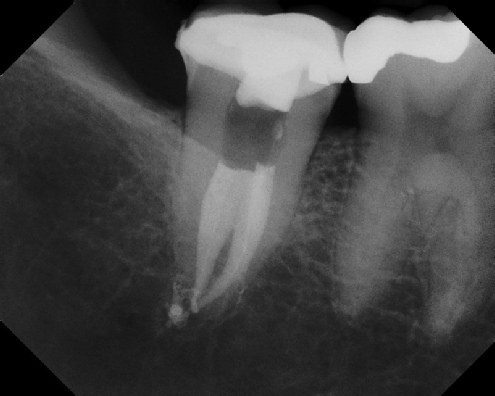

To view radiographic examples of the various types of root canal

cases we routinely treat, click on any of the categories shown below.

COMPLICATED ANATOMY LARGE LESIONS CALCIFIED CANALS PERFORATION / RESORPTION SEPARATED INSTRUMENTS SURGICAL CASES RETREATMENT / pOST REMOVAL OPEN APICES ACCESS THRU CROWNS Root Canal Case Portfolio Root Canal Specialists - Joel B. Chasen DMD, Joshua Dembsky DMD, Elinor Alon DMD, Shimona Malik DMD

Root Canal Anatomy - Meriden root canal anatomy - Meriden